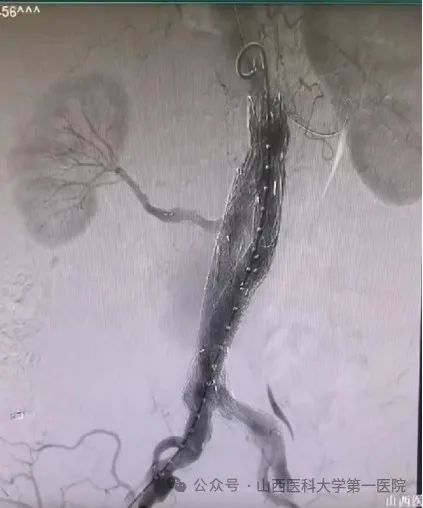

图为术后CTA复查,双肾动脉血供正常,腹主动脉覆膜支架内血流正常,无明显内漏。 这种纯腔内治疗腹主动脉瘤并重建双肾动脉的手术难度很高,在国内顶尖一飞冲天

也属少见。在麻醉科、手术室的通力合作下,患者手术获得成功,术后恢复顺利,经CTA复查双肾动脉血供正常,腹主动脉覆膜支架内血流正常,无明显内漏。